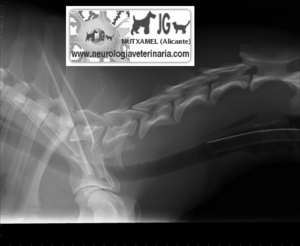

Galgo con atrofia de musculatura escapular por denervación motivada por fractura de escápula |